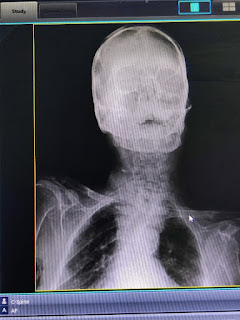

Xrays: